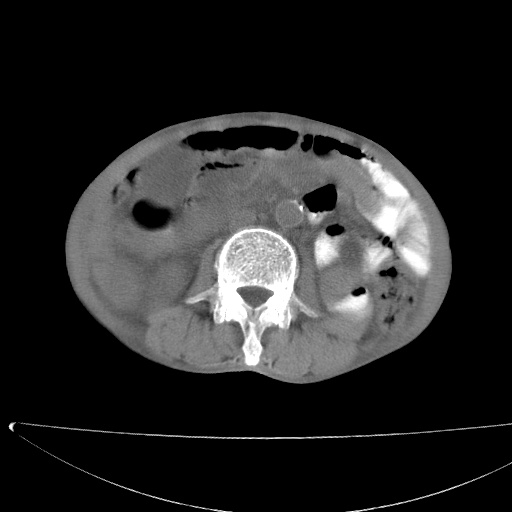

患者男70岁,上腹部不适1月。8年前有胃癌手术史。余病史不祥。

考虑胃癌复发并小网膜淋巴结转移侵及肝脏胆总管梗阻

考虑胃癌复发并腹腔内淋巴结转移。

1)胃癌术后,复发不排除。

2)肝脏转移瘤。

3)肝脏钙化灶。

4)胆囊增大。

5)腹膜后多发性淋巴结转移。

6)腹水。

建议:增强扫描。

考虑胃窦癌肝门转移

考虑胃癌复发并腹腔内淋巴结转移,胆总管受侵。

考虑胃窦癌肝门区淋巴结转移!

1)胃癌术后,不排除复发可能。2)考虑肝脏及腹膜后淋巴结转移瘤。3)肝内胆管扩张,胆囊增大。4)肝内胆管结石(或钙化)。5)脾脏钙化灶。6)腹水。7)右侧少量胸腔积液。

建议:行ct增强扫描检查。

1、胃癌根治胃空肠吻合术后,残胃癌?

2、肝门区占位性病变并胆道上段梗阻(肝内胆管扩张、胆囊增大),考虑肝门区淋巴结转移累及胆总管,建议ct增强扫描;

3、右侧胸腔少量积液、少量腹水;

4、肝右叶胆管结石。

肝门区占位性病变并肝内胆管扩张。

小网膜囊区及腹膜后肿大淋巴结。